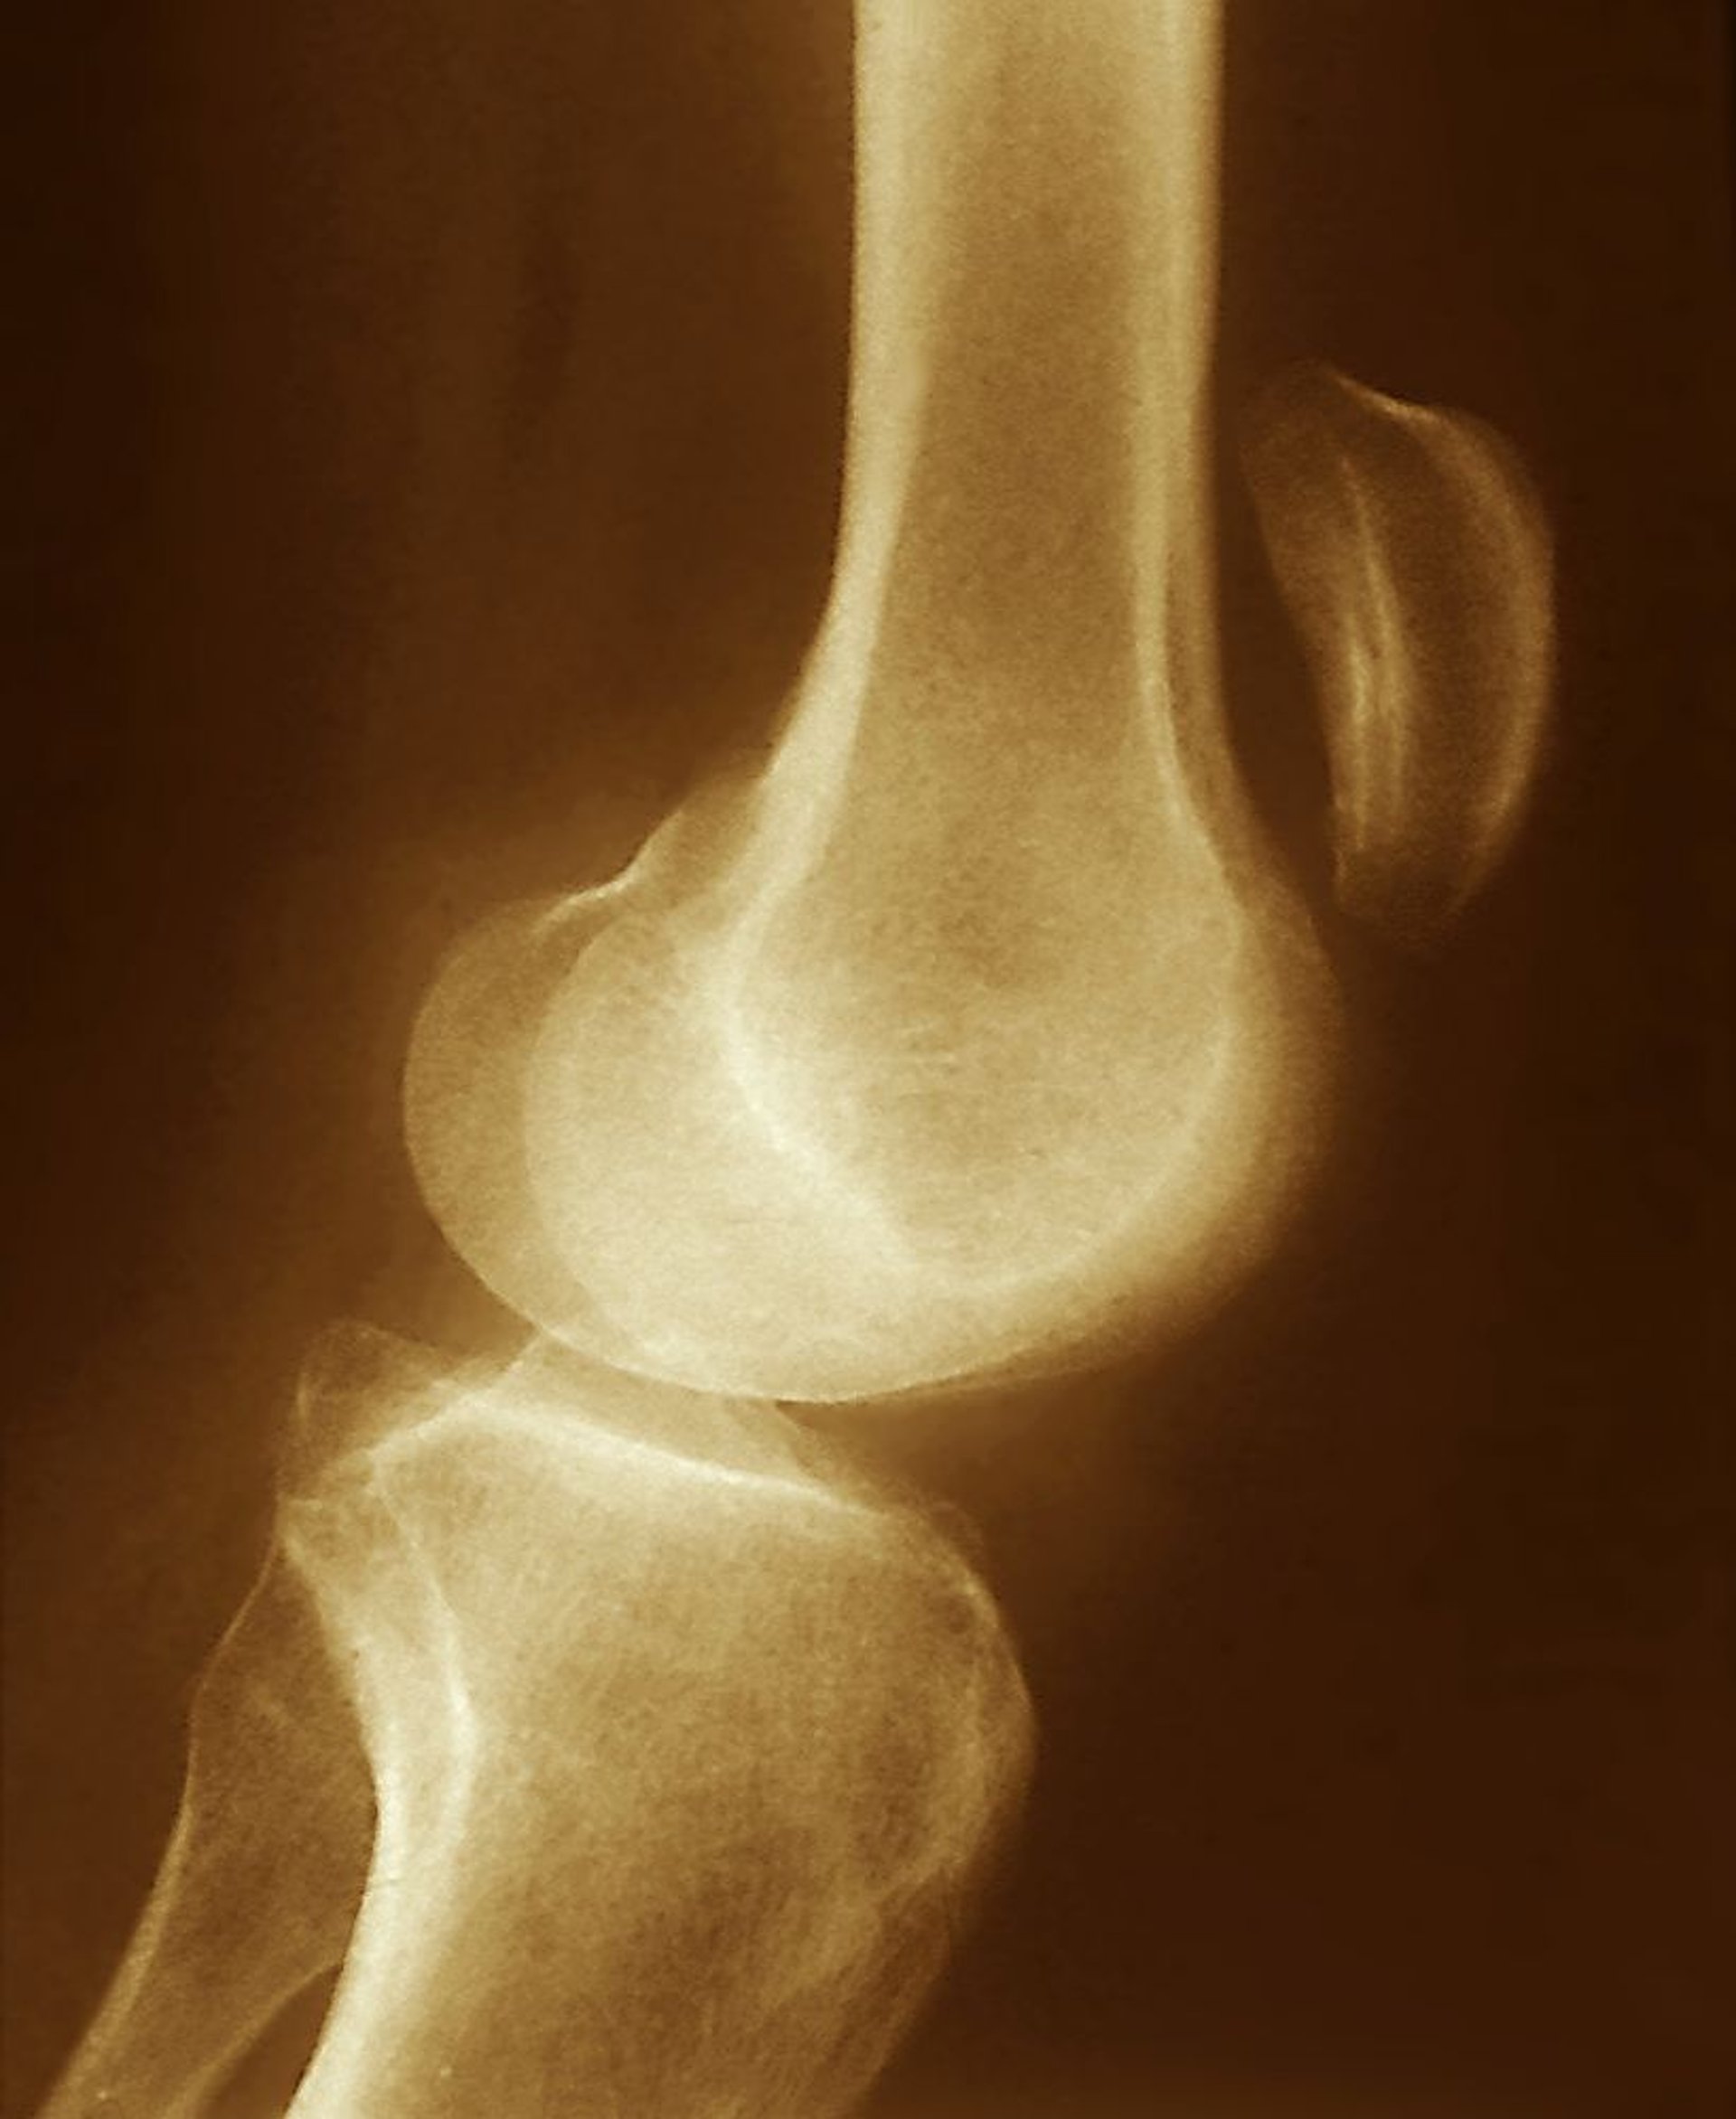

Desgarro del tendón rotuliano

El desplazamiento superior de la rótula visto en esta radiografía (muy por encima de la articulación de la rodilla) sugiere un desgarro del tendón rotuliano, con contracción del músculo cuádriceps sin oposición.